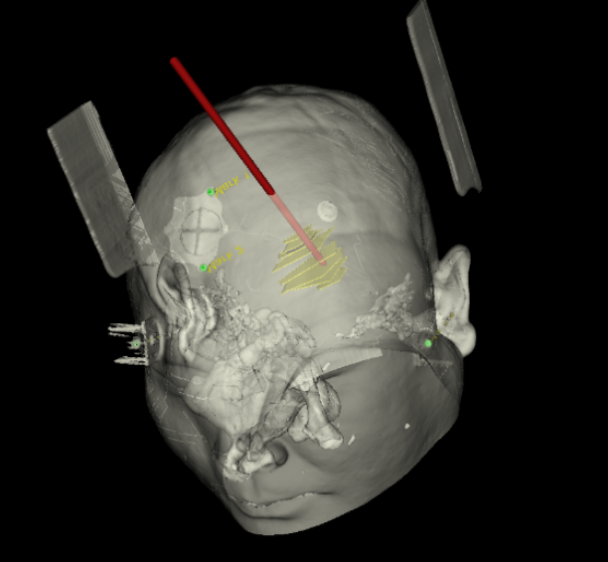

手術(shù)日當(dāng)天,醫(yī)生團隊通過手術(shù)計劃系統(tǒng)為患者制定手術(shù)靶點及最安全的入顱路徑,隨后將手術(shù)規(guī)劃導(dǎo)入手術(shù)室的機器人當(dāng)中。

實際手術(shù)時,機器人在幾分鐘內(nèi)就完成了空間注冊,機械臂在定位儀的引導(dǎo)下自動定位,準(zhǔn)確鎖定靶點。

術(shù)前韓帥醫(yī)生使用“睿米”制定手術(shù)規(guī)劃

手術(shù)規(guī)劃在機器人軟件上制定完成